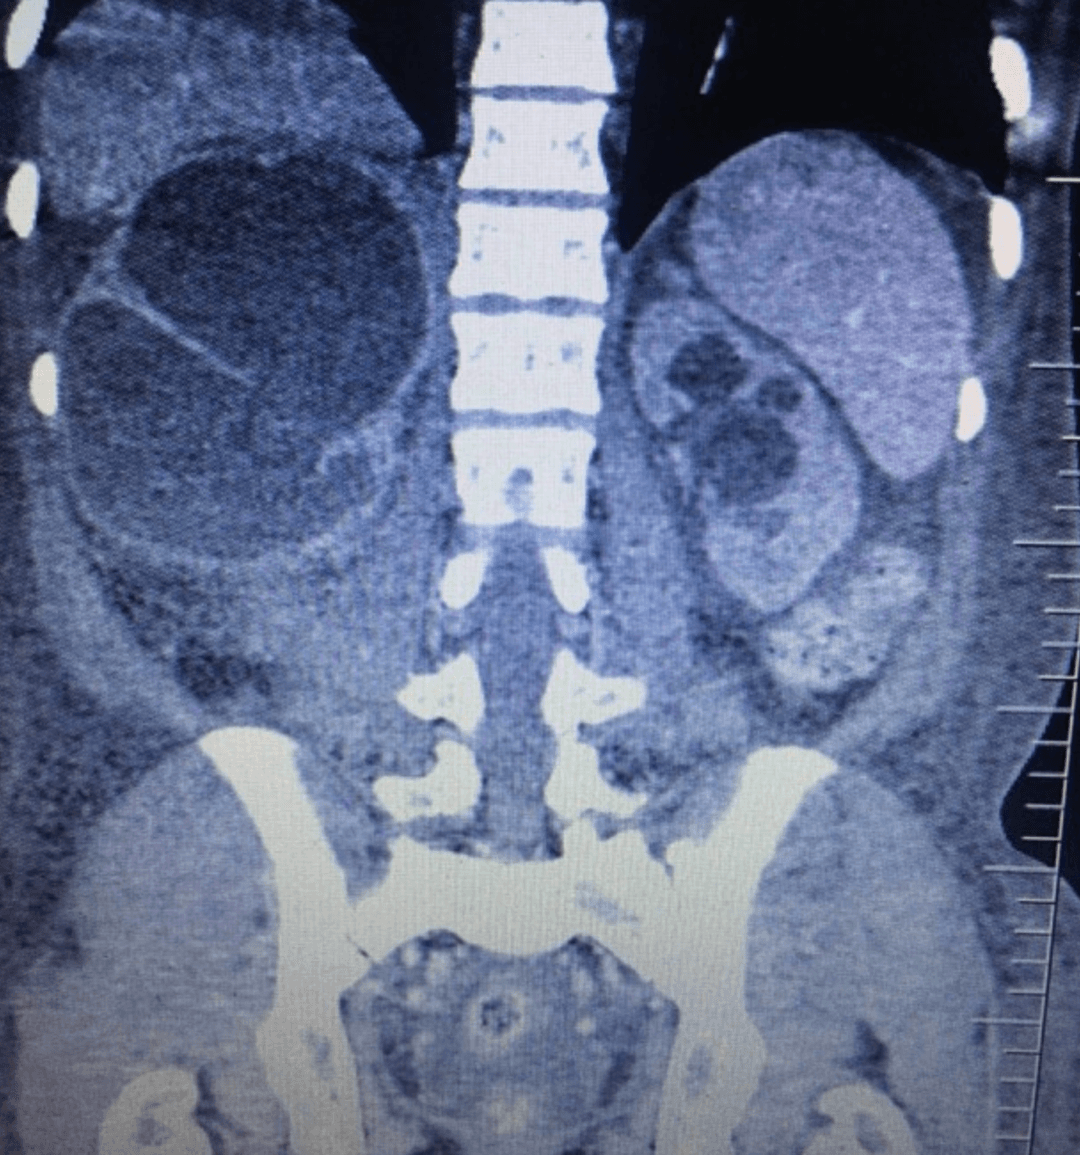

Initial laboratory testing shows WBC 3.8 x 10^9/L, hemoglobin 6.0 g/dL, MCV 92 fL, platelets 187 x 10^9/L, creatinine 12.1 mg/dL, BUN 250 mg/dL, and potassium 7.2 mmol/L. Chest radiography shows an enlarged cardiac silhouette with lower-zone hazy opacification consistent with pulmonary edema. CT abdomen and pelvis demonstrated massive right-sided hydroureteronephrosis and moderate left-sided hydronephrosis.

CT abdomen and pelvis demonstrating massive right-sided hydroureteronephrosis.